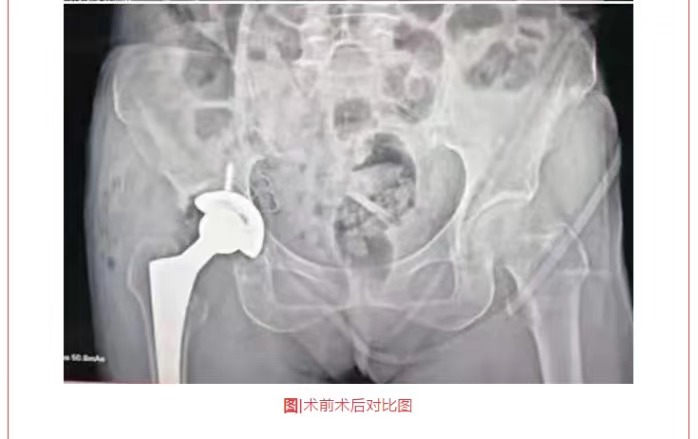

熱烈祝賀穗康長貞醫(yī)院成功完成兩例全髖關節(jié)置換術(shù)

惠東穗康長貞醫(yī)院一直以來本著“生命至上、以人為本”的職業(yè)理念,以“服務社會、取信于民”為追求,在黃寶壬董事和陳啟海院長的領導下,不忘初心,砥礪前行,不斷提高技術(shù)服務、持續(xù)加強醫(yī)療服務,以救死扶傷為本職,還廣大市民一份健康。